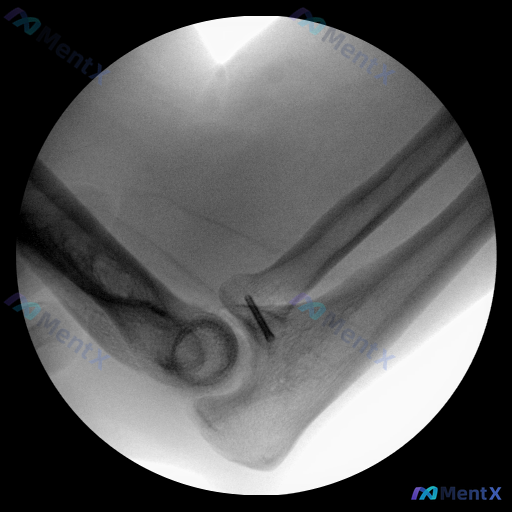

整理到一份肘关节的影像资料,先不放太多背景,仅看这张X光(侧/斜位):

- 肱骨远端、尺骨近端、桡骨头的骨皮质轮廓大致清晰,关节对位尚好

- 关键异常:在尺骨近端与肱骨远端关节间隙的前方,可见一枚线状高密度金属阴影,横穿部分关节间隙或邻近骨结构

- 金属影附近的尺骨冠突区域,因遮挡无法完全排除微小骨折

- 无明显软组织肿胀、关节游离体或广泛骨赘